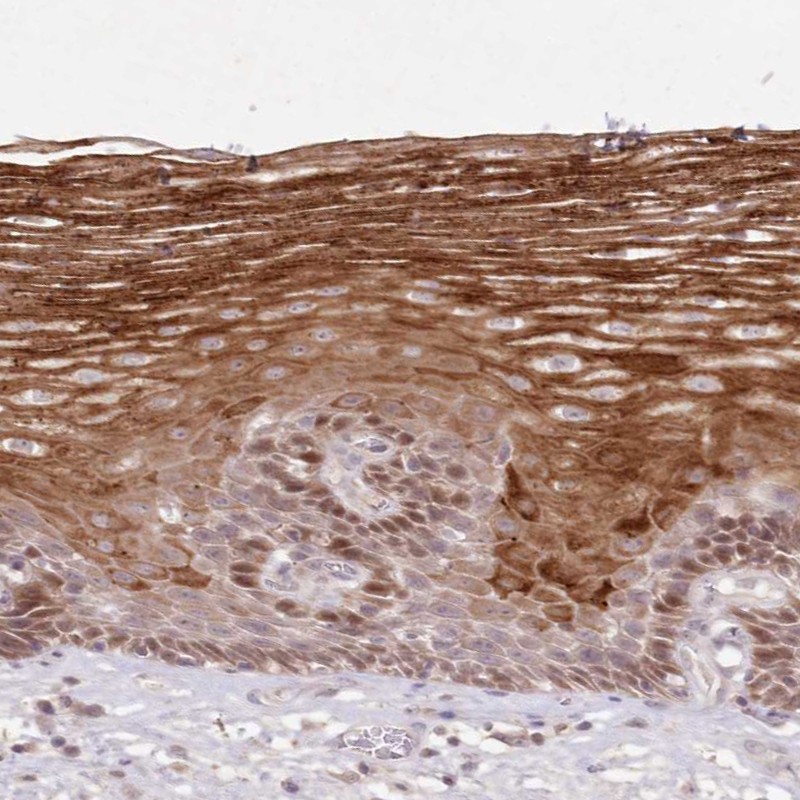

Immunohistochemical staining of human esophagus shows strong cytoplasmic positivity in squamous epithelial cells.